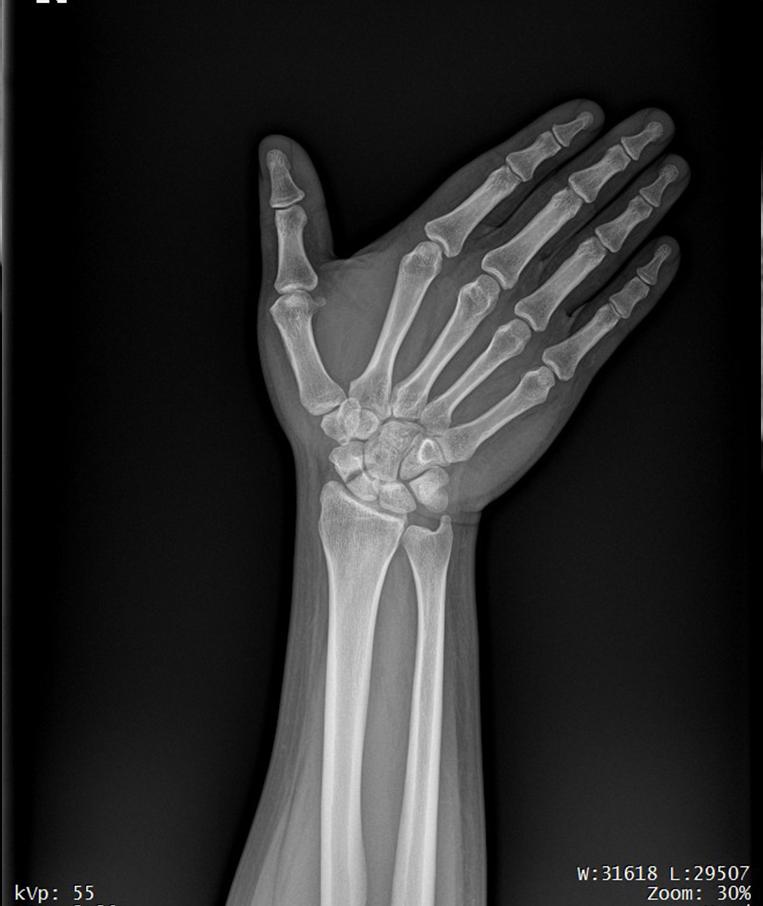

Clinical picture

临床图片